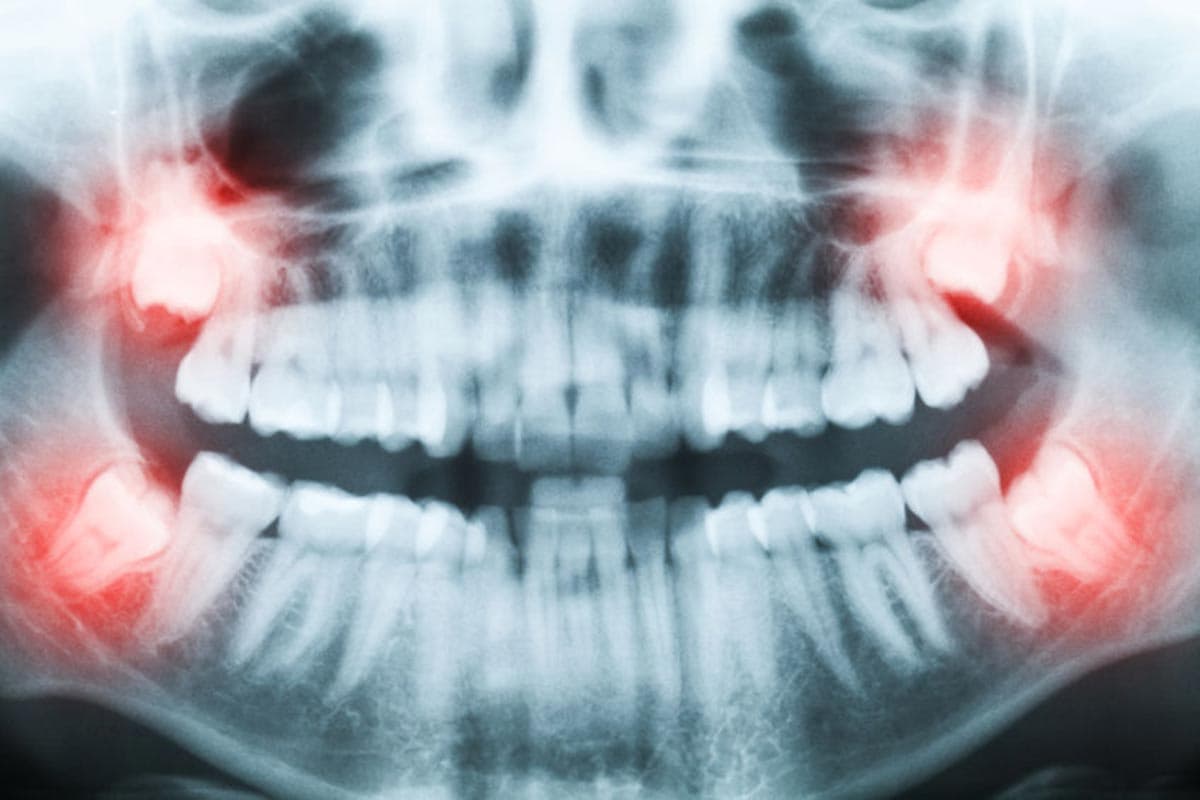

Comprehensive oral surgery including impacted wisdom teeth extraction, complex tooth removal, surgical exposure of impacted teeth for orthodontics, TMJ disorder treatment (temporomandibular joint surgery), cyst and tumor removal, and pre-prosthetic surgery. All procedures are performed under comfortable IV sedation or general anesthesia at our fully equipped Roseville surgical center. Dr. Antipov is fellowship-trained to handle even the most complex cases with precision and care.